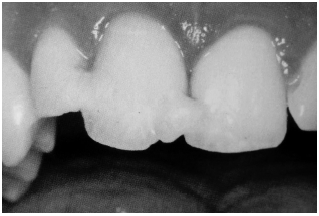

Fractures of the Crown. Crown fractures may be divided into uncomplicated and complicated categories. Uncomplicated crown fractures involve the enamel or enamel and dentin. (See Figure 1.)

Crown fractures through the enamel usually are not sensitive to forced air, hot or cold, or percussion and usually pose no threat to the dental pulp. Immediate treatment in the ED is not necessary but may consist of smoothing the sharp edges off the tooth with an emery board or small hand-held disc sander. It is very important to reassure the patient that a dentist can restore the tooth to its natural appearance using composite resins and bonding materials. Follow-up is important, as pulp necrosis rarely can occur as can color change (0-3%).2,18 (See Figures 1 and 2.)

| Figure 2. Enamel Damage |